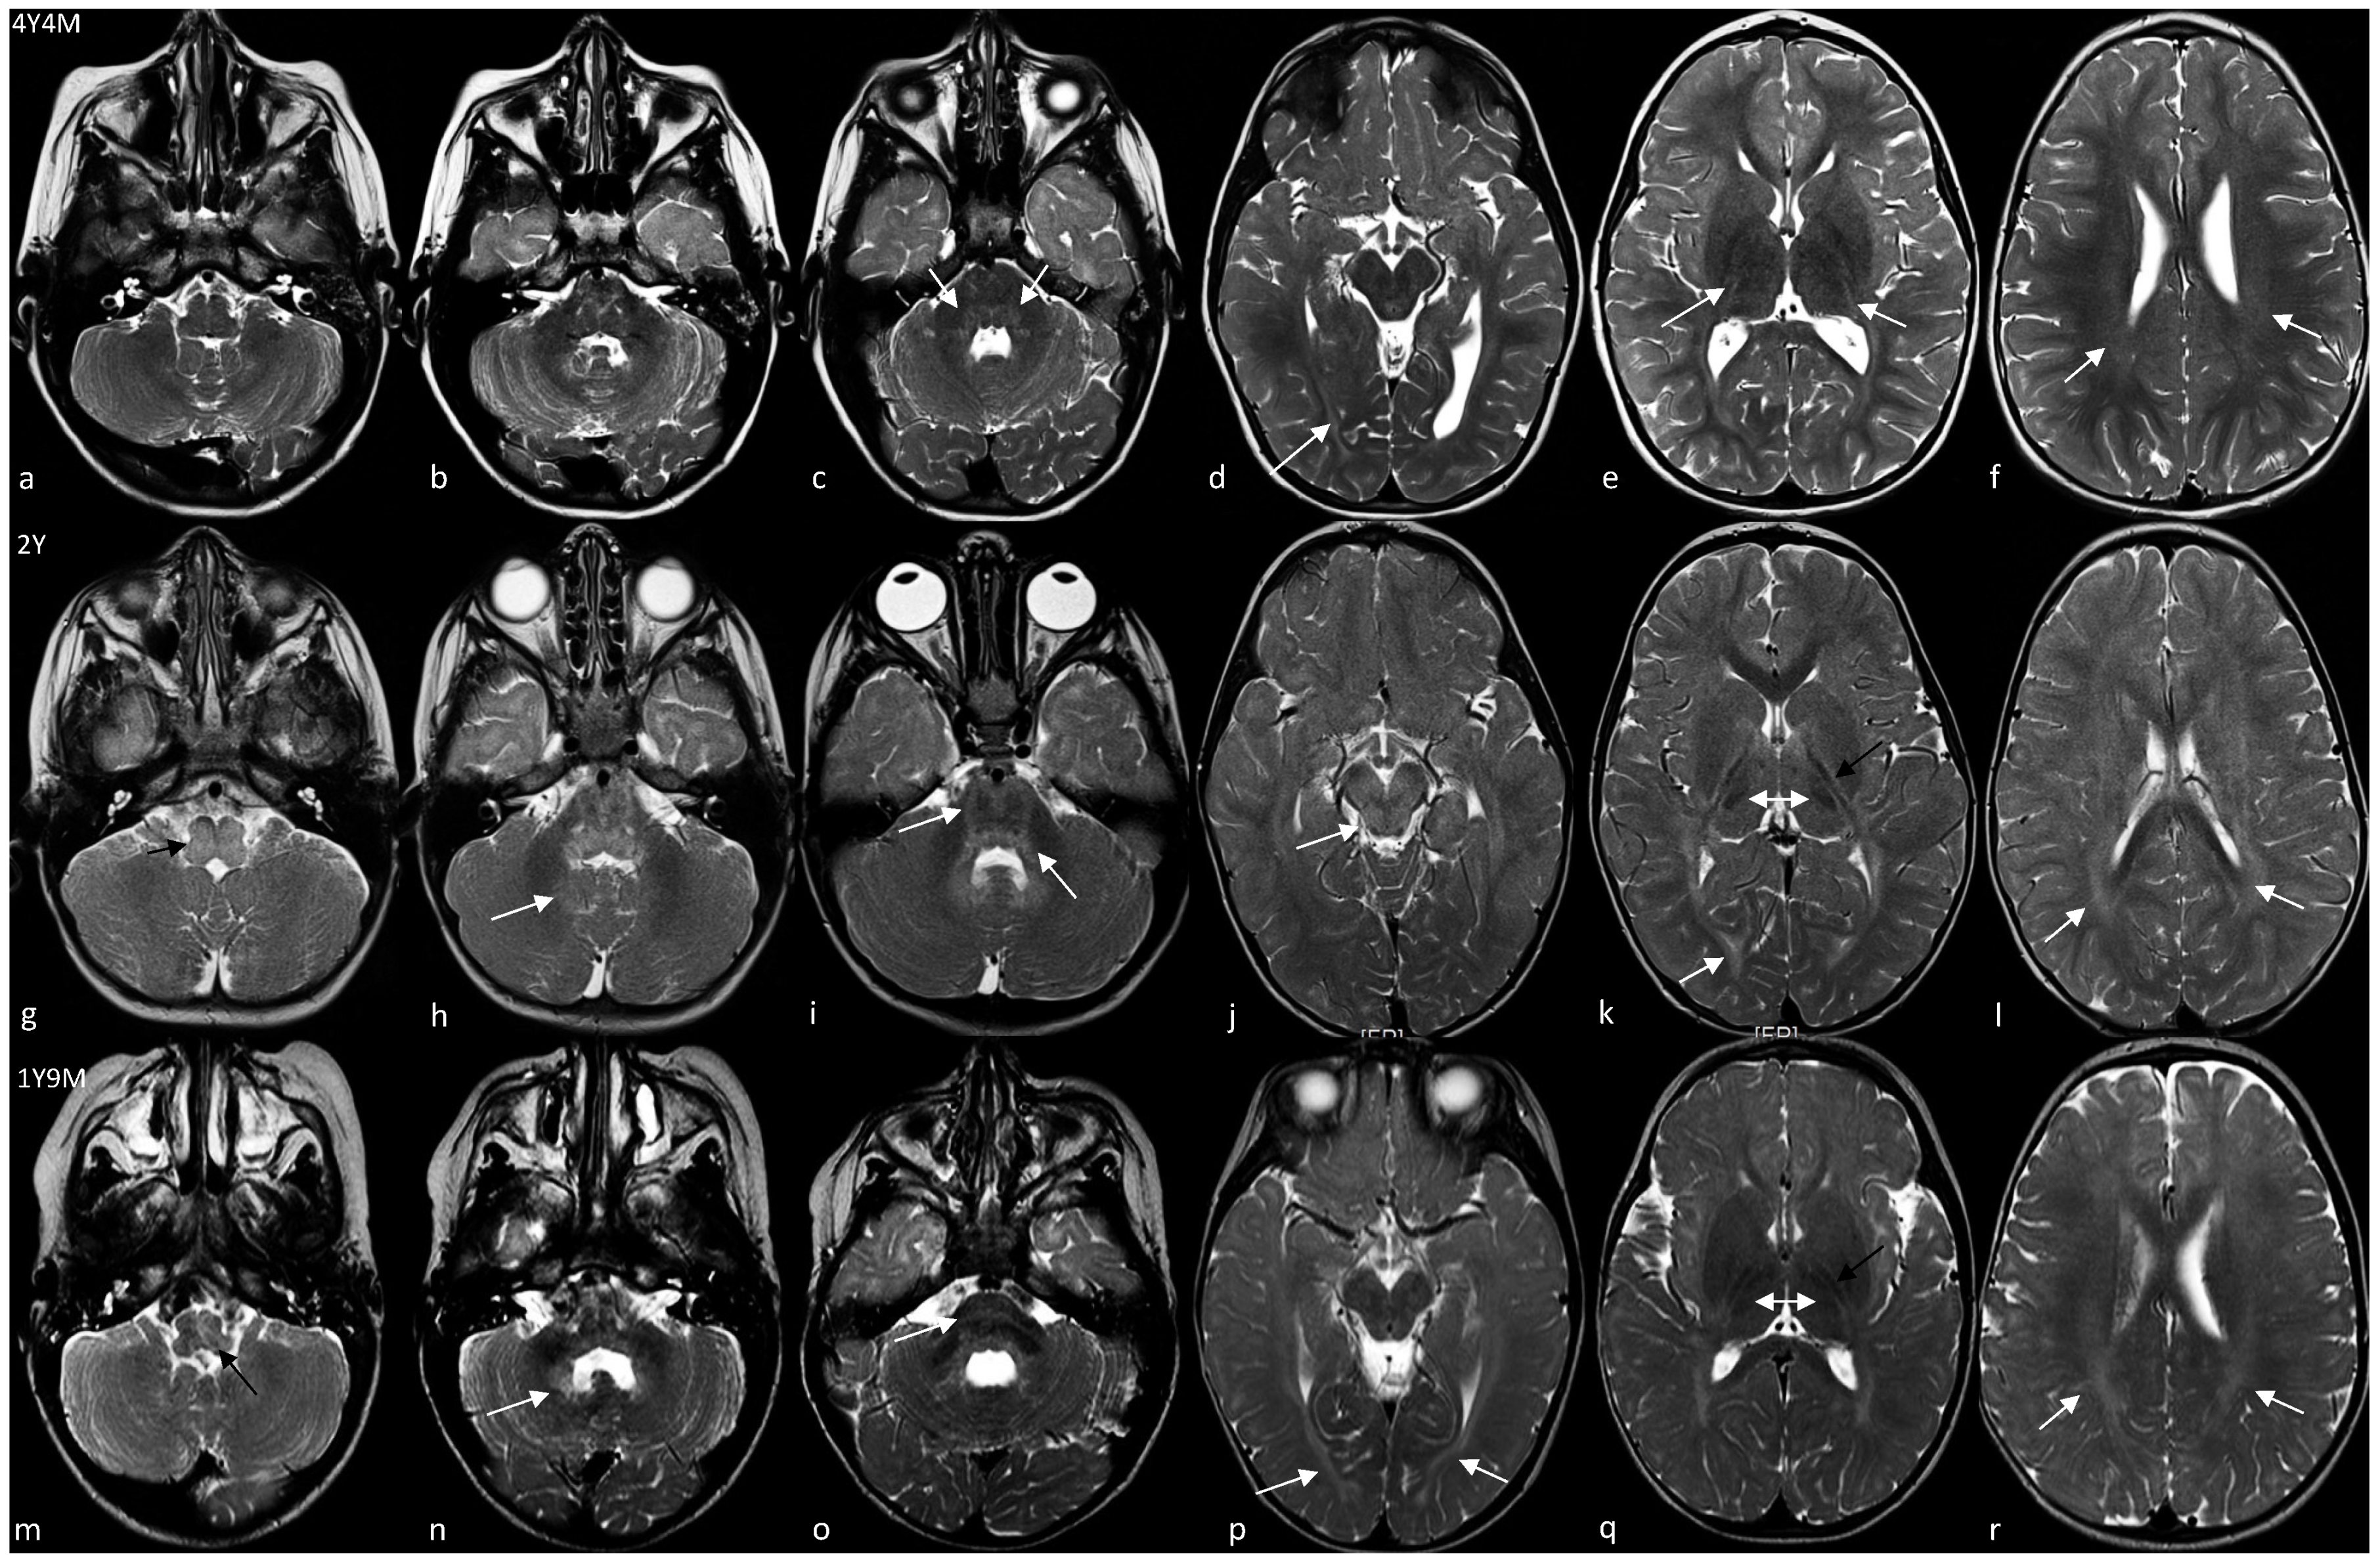

Patient 1 is a 5.5-year-old boy with a history of psychomotor delay and hypotonia in the first year, followed by slow improvement over the years. He was born at term after uneventful pregnancy by cesarean delivery due to fetal macrosomia (i.e., weight greater than 4000 g regardless of baby’s gestational age). When he came to our attention, at the age of 4, neurological examination showed an ataxic gait with upper limbs tremor and dysarthria; osteotendinous reflexes were only mildly increased at lower limbs without further pyramidal signs. Brain MRI showed mild signs of hypomyelination (i.e., an increased signal in the T2/FLAIR images) with the involvement of pons, periventricular white matter, and posterior limb of internal capsulae (PLIC) (Figure 2a–f, Table 2) that remained unchanged one year later (data not shown). Nerve conduction study was normal. Visual evoked potential (VEP) showed bilateral increased latency. Brainstem auditory evoked potentials (BAEPs) detected upper pontine alterations. Currently, he is able to walk with little support and speak with simple sentences. No episodes of regression have been recorded.

Patient 2 is a 3 year 4 months old child born at term by cesarean section due to advanced maternal age. Pregnancy was uneventful, as well as delivery and neonatal period. Pendular nystagmus appeared at age 6 months and was followed by a delay in motor and language development. Brain MRI at the age of 2 showed signs of hypomyelination at the level of the medulla and pons, dentate nuclei, optic radiations, PLIC with tram track appearance, white matter of periventricular regions and corona radiate (Figure 2g–l, Table 2). At last evaluation, the child showed an ataxic–spastic syndrome, but was able to walk and run; nystagmus improved. He could speak with appropriate language for his age.

Patient 3 is an 8-year-old boy born at term by caesarean delivery for premature rupture of membranes with meconium-stained in amniotic fluid during labor. Apgar scores were 9-9 at 1′ and 5′ minutes, respectively. He started manifesting a psychomotor delay by the age of 9 months. At the age of 1 and a half years, the child could not sit unsupported, and a language delay was also evident. The neurological evaluation showed strabismus, axial hypotonia, and pyramidal hypertonia of lower limbs. Brain MRI revealed increased signal in the T2/FLAIR images with the involvement of medulla and pons, dentate nuclei, optic radiations, PLIC with tram track appearance, white matter of periventricular regions, and corona radiata (Figure 2m–r, Table 2) consistent with hypomyelination. Visual evoked potential revealed a bilateral reduction of amplitude and delayed latencies. Over the years, the child showed slow improvement in motor and cognitive function without evidence of neurodegeneration. A further brain MRI revealed some modifications of a hypomyelinating pattern (Table 2, Figure S1). At the last examination, at the age of 8, he manifested strabismus, drooling, head and trunk titubation, intentional tremor of upper limbs. Dyskinetic orofacial movements were also recorded, and therapy with tetrabenazine was prescribed. Pyramidal spasticity of lower limbs was evident and required focal treatment with botulin injection. Currently, he attends elementary school with a support teacher; he is able to sit with lateral support, to walk some steps with a walker, and to use a wheelchair for long distances. He has a moderate ability to push the wheelchair independently. The speech is impaired with dysarthria and words are difficult to understand most of the time. In the same family, the 46-year-old maternal uncle (patient 4) had a similar clinical history. Specifically, he was born at term with premature rupture of membranes and labor dystocia. At birth, he showed mild signs of hypoxic-ischemic encephalopathy but no further treatment was started at that time. Psychomotor delay and hypertonic syndrome were evident from the first year of life, but no investigations were carried out. He developed spastic ataxia over the years, and was able to walk with lateral support from the age of 2.5 to 20 years when he lost the ability to walk due to worsening of motor functions. At last examination, at the age of 46, he showed spastic tetraparesis with cerebellar signs, was wheelchair-bound and had no swallowing problems. His speech was unintelligible and he was completely dependent for activities of daily living.

Brain MRI confirmed the involvement of structures that physiologically myelinate early, specifically brainstem, PLIC, and optic radiations. Interestingly, brain MRI did not show any involvement of medulla, midbrain, and hilus of the dentate nuclei in the single case (i.e., patient 1) who had his first neuroradiological study performed after the age of 2. As reported in several HEMS cases by Kelavam and colleagues [2], improvement of myelination of some structures (e.g., medulla, pons, dentate nuclei) and worsening in others (e.g., periventricular white matter) have also been observed in patient 3. Consequently, these data suggest that the pattern of hypomyelination in HEMS may change over time and may be related to the age at which brain MRI is performed, but the involvement of some structures (i.e., PLIC, optic radiations) is mandatory and can be considered as the neuroradiological hallmark of the disease and generally does not change with time.

Figure 2. T2-weighted axial brain MRI of patient 1 (af), 2 (gl), and 3 (mr). In patient 1, medulla (a), dentate nuclei (b), and (d) midbrain are spared while mild hyperintensity is observed in dorsal pons (white arrows in c), optic radiations (white arrow in d), PLIC (white arrows in e) and periventricular white matter (white arrows in f). Patients 2 and 3 showed a more similar pattern of anomalies, with a high signal of the medulla (black arrow in g and m), hilus of the dentate nuclei (white arrow in h and n), pons (white arrow in i and o), optic radiations (white arrow in k and p) and periventricular white matter (white arrows in l and r). Please also note that the midbrain is hyperintense only in patient 2 (white arrow in j), that PLIC has a typical tram track appearance (black arrow in k and q), and that the dorsomedial thalami are hyperintense compared to the ventrolateral part (double white arrows in k and q).